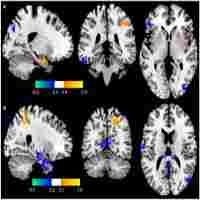

| Abstract | Background Repetitive transcranial magnetic stimulation (rTMS) has shown promising efficacy in improving the language functions in poststroke aphasia. However, randomized controlled trials were lacking to investigate the rTMS-related neuroimaging changes underlying the therapeutic effects on language improvement in chronic aphasia. Objective In this study, we aimed to evaluate the effects of low-frequency rTMS (LF-rTMS) on chronic poststroke aphasia. We hypothesized that the deactivation of the right pars triangularis could restore the balance of interhemispheric inhibition and hence facilitated the functional remodeling of language networks in both hemispheres. Furthermore, the rTMS-induced functional reorganization should underpin the language recovery after rTMS. Methods A total of 33 patients (22 males; ages: 58.70±13.77 years) with chronic stroke in the left hemisphere and nonfluent aphasia were recruited in this randomized double-blinded study. The ratio of randomization between rTMS and sham group is 17:16. All patients received real 1-Hz rTMS or sham stimulation (placebo coil delivered <5% of magnetic output with similar audible click-on discharge) at the right posterior pars triangularis for 10 consecutive weekdays (stroke onset to the first stimulation: 10.97±10.35 months). Functional connectivity of language networks measured by resting-state fMRI was calculated and correlated to the scores of Concise Chinese Aphasia Test using the stepwise regression analysis. Results After LF-rTMS intervention, significant improvement in language functions in terms of comprehension and expression abilities were observed compared with the sham group. The rTMS group showed a significant decrease of coupling strength between right pars triangularis and pars opercularis with a strengthened connection between right pars orbitalis and angular gyrus. Furthermore, the LF-rTMS significantly enhanced the coupling strength associated with left Wernicke area. Results of regression analysis showed that the identified functional remodeling involving both hemispheres could support and predict the language recovery after LF-rTMS treatment. Conclusions We reported the therapeutic effects of LF-rTMS and corresponding functional remodeling in chronic poststroke aphasia. Our results provided neuroimage evidence reflecting the rebalance of interhemispheric inhibition induced by LF-rTMS which could facilitate future research in the refinement of rTMS protocol to optimize the neuromodulation efficacy and benefit the clinical management of stroke patients. |